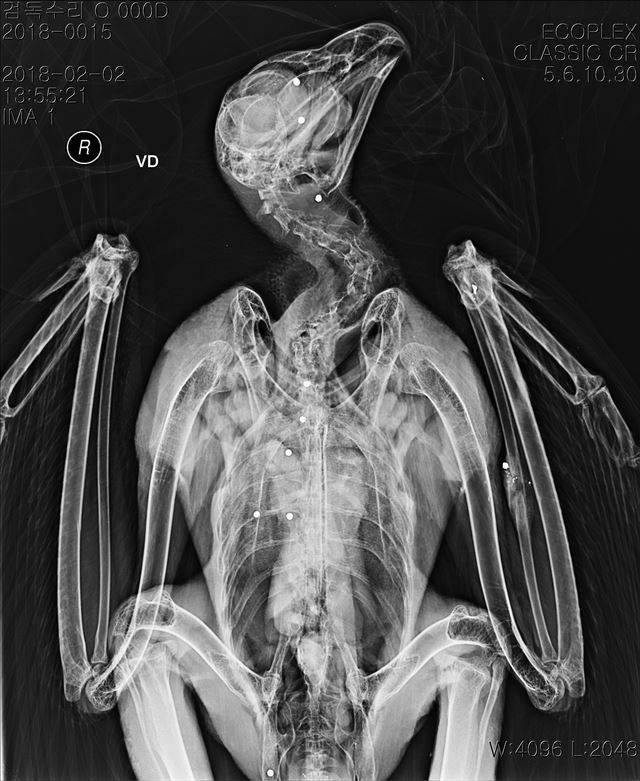

[애니칼럼] 먹잇감의 심장까지 꿰뚫는 진짜 '하늘의 제왕' 검독수리

글ㆍ사진 김영준 국립생태원 동물병원 부장